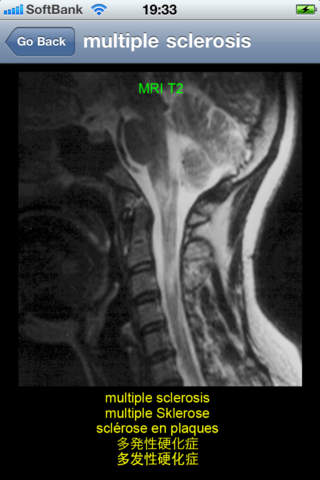

This application is developed to study neuroradiology in English, German, French, Japanese, and Chinese for medical students and professionals such as physicians and nurses. It consists of 26 diagnosis: acoustic neurinoma, acute epidural hematoma, ADEM, aneurysm, arachnoid cyst, arteriovenous malformation, astrocytoma, cerebellar atrophy, cerebral embolism, cerebral hemorrhage, cerebral infarction new and old, cervical disc herniation, chronic subdural hematoma, colon carcinoma metastasis, depressed skull fracture, glioblastoma multiforme, hemorrhagic infarction, meningioma, multiple sclerosis, OPLL, osteoma, pineal cyst, pontine hemorrhage, putaminal hemorrhage, subarachnoid hemorrhage, and syringomyelia.